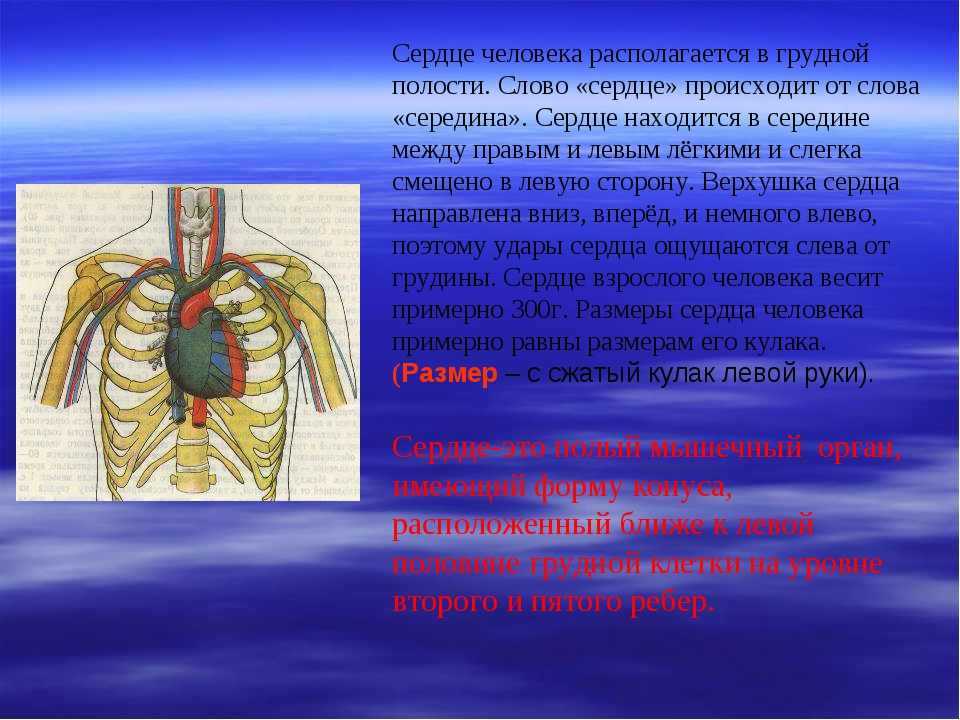

С какой стороны сердце у человека.

Где находится сердце у человека.

Сердце у человека располагается.

Сердце у человека располагается в грудной полости.

Расположение сердца у человека.

Анатомическое расположение сердца.

Сердце в грудной клетке расположено.

Где расположено сердце у человека анатомия.